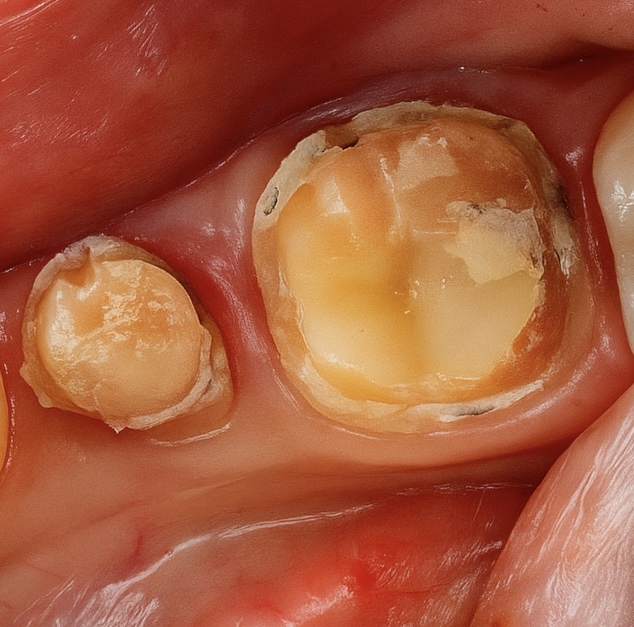

5. Core Build-Up and Preparation

A dual-cure resin core (Clearfil DC Core Plus) was bonded using 4th-generation adhesive (Clearfil SE Bond 2). Tooth preparation followed the principles of adhesive ferrule preservation with rounded internal line angles (Fig 2).

- Fig 2: Post-endodontic core build-up and crown preparation.